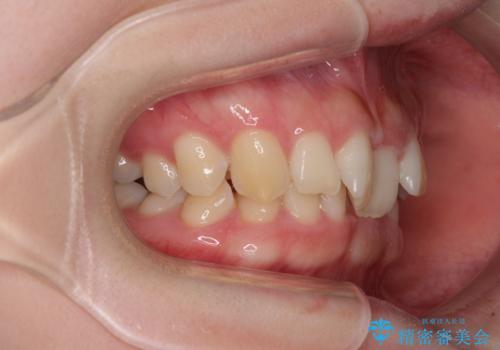

奥歯の咬み合わせを見ると、片方は上顎が下顎に対して相対的に前方にあり、他方は交叉した咬合の状態でした。

咬み合わせを改善するためには、上顎臼歯を後方に移動させた咬み合わせにする必要があります。

インビザライン単体で改善することも可能ですが、ディープバイトのためインビザライン単体で達成する可能性が低いと考えられたため、カリエール・ディスタライザーという補助装置を併用して、より確実性を上げることとしました。

カリエール・ディスタライザーを使用している期間、反対側はワイヤー矯正により叢生を解消していくこととしました。

奥歯の咬み合わせを改善しながら、並行してインビザラインで歯列を整えることとしました。

カリエールディスタライザーやワイヤー矯正を併用したことで、確実かつ短期間で治療を終えることができました。